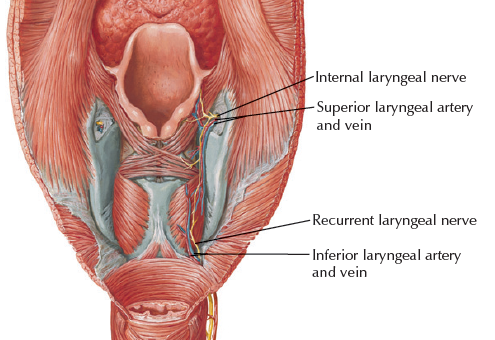

Artery

Nerve

- Sup. laryngeal n.

- Internal br.(Internal laryngeal n.)

- Sensor

- 穿過 Thyrohyoid ligament

- External br.

- Motor

- Internal br.(Internal laryngeal n.)

- Recurrent laryngeal n.

- Inf. laryngeal a.伴行

- 過Cricothyroid joint改叫Inf. laryngeal n.